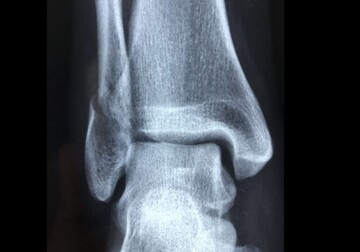

Pe măsură ce oamenii îmbătrânesc, oasele își pierd natural densitatea și devin mai poroase. În interiorul măduvei osoase se află celule stem mezenchimale, care se pot transforma fie în țesut osos, fie în celule adipoase (grăsime).

În mod normal, aceste celule răspund la forțele fizice (mișcare, presiune). Totuși, îmbătrânirea înclină balanța, făcând ca mai multe celule stem să se transforme în grăsime, în detrimentul țesutului osos, care ajunge să slăbească. Se ajunge la un ciclu de deteriorare dificil de inversat prin terapiile actuale.

În urma experimentelor pe modele de șoareci și celule stem umane, cercetătorii au identificat o proteină numită Piezo1 pe suprafața celulelor stem din măduva osoasă. Această proteină funcționează ca un senzor mecanic, care detectează forțele generate în timpul exercițiilor fizice. Când simte aceste mișcări se formează țesut osos. Când nu, țesut adipos.